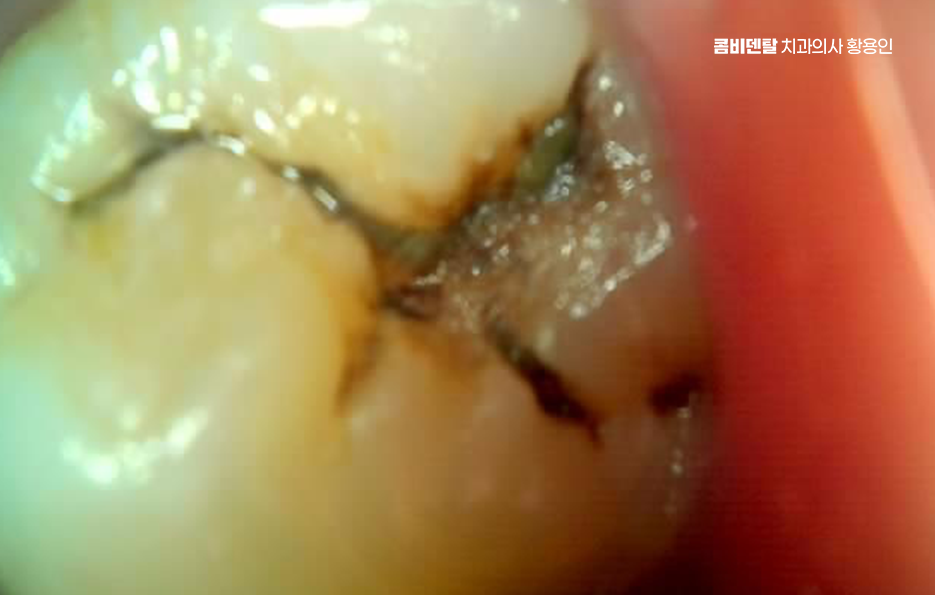

어금니 충치 단계 법랑질을 넘어 상아질까지 진행되면 상황이 달라지는데 상아질은 법랑질보다 부드럽고 신경과 가까워서 2단계에서는 차가운 것에 시린 느낌이 들 수 있어요.

단 음식을 먹었을 때 찌릿하게 느껴지기도 하는데 통증은 자극이 있을 때만 나타나고, 자극이 사라지면 비교적 금방 가라앉는 특징이 있으며 어금니 충치 단계 2단계에서는 충치 범위가 넓어져 단순 레진보다는 인레이 같은 간접 보철 치료가 필요한 경우도 있으며 삭제 범위가 커지기 때문에 치아 형태를 정밀하게 복원하는 것이 중요한 단계라고 할 수 있었어요

더 진행되면 신경에 가까워져 통증이 뚜렷해지며 뜨거운 음식에 욱신거리고, 통증이 오래 지속될 수 있고 밤에 통증이 심해지는 경우도 있는데 이는 신경 염증이 시작되었다는 신호일 수 있었어요.

이 단계에서는 단순 충치 치료로는 해결이 어렵고, 신경치료가 필요할 가능성이 커지며 감염된 신경 조직을 제거하고 내부를 소독한 뒤 밀봉하는 과정을 거치게 되는데 이후에는 치아가 약해지기 때문에 크라운으로 덮어 보호하는 경우가 일반적이라 할 수 있어요